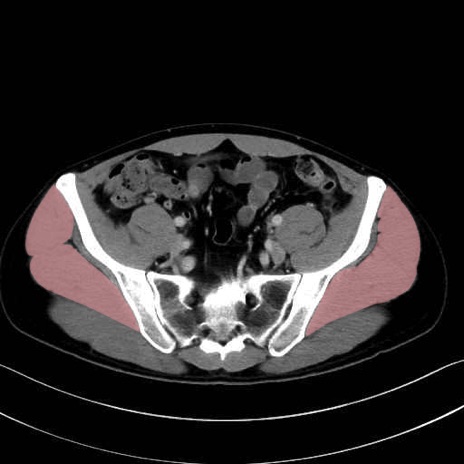

中殿筋 (Gluteus medius)